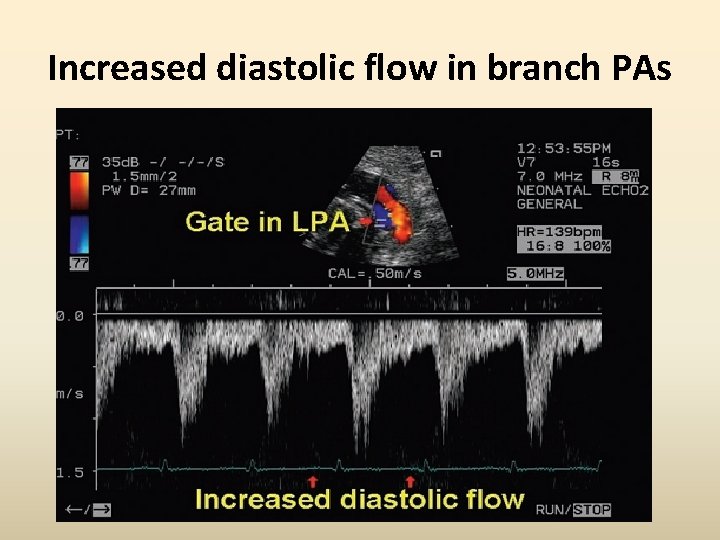

Increased diastolic flow in branch PAs